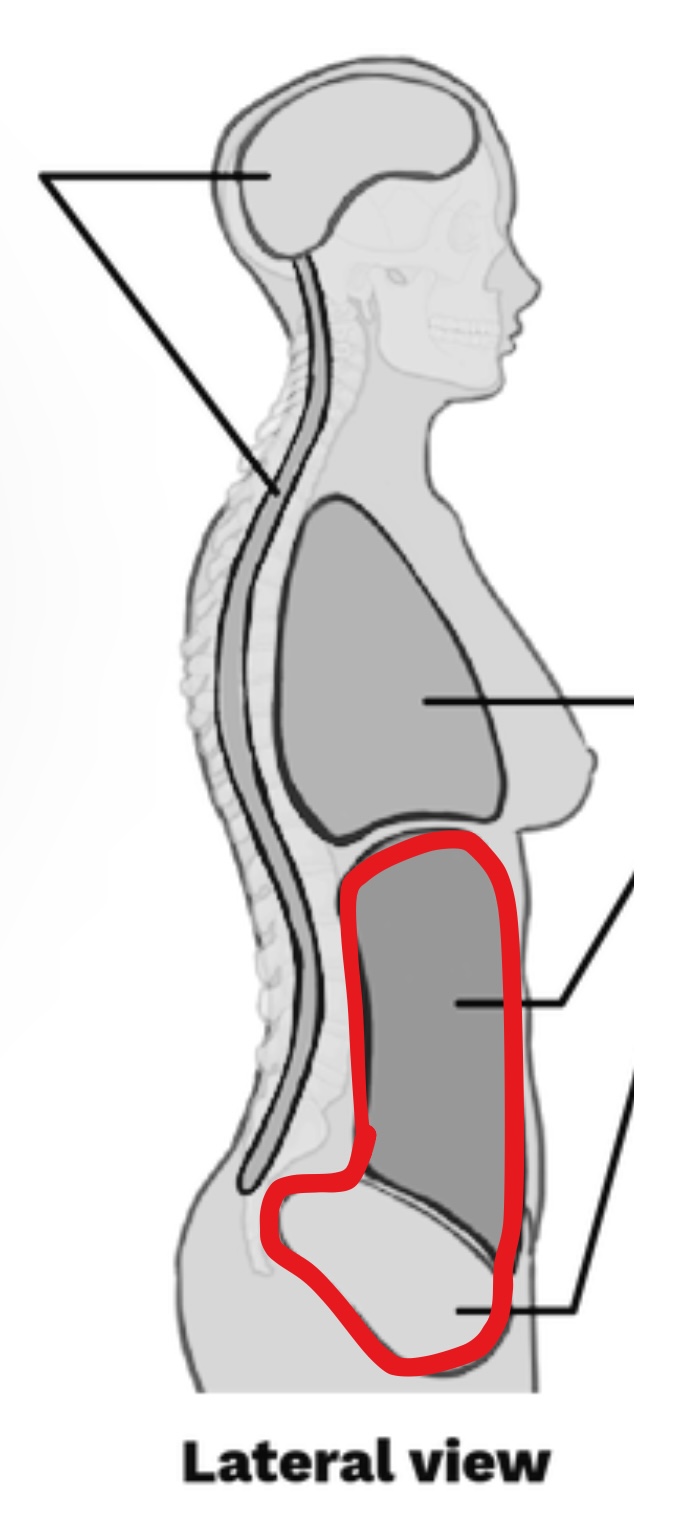

What cavity is this?

Abdominopelvic Cavity